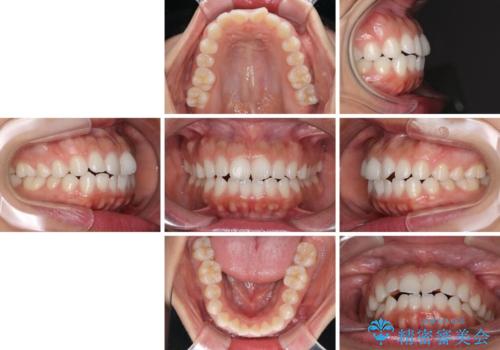

目立たない装置で横顔のシルエットを改善 ハーフリンガルでの抜歯矯正

- 口元の突出感を気にして来院された患者様です。

上下左右の第一小臼歯4本を抜歯して口元を下げる治療計画としました。